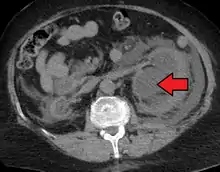

Renal ultrasonography of hydronephrosis caused by a left ureteral stone.

Imaging studies, such as an intravenous urogram (IVU), renal ultrasonography, CT, or MRI, are also important investigations in determining the presence and/ or cause of hydronephrosis. Whilst ultrasound allows for visualisation of the ureters and kidneys (and determine the presence of hydronephrosis and / or hydroureter), an IVU is useful for assessing the anatomical location of the obstruction. Antegrade or retrograde pyelography will show similar findings to an IVU but offer a therapeutic option as well. Real-time ultrasounds and Doppler ultrasound tests in association with vascular resistance testing helps determine how a given obstruction is effecting urinary functionality in hydronephrotic patients.[9]